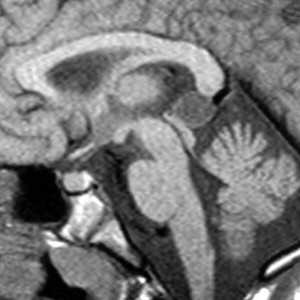

МРТ головного мозга. Сагиттальная Т1-взвешенная МРТ. Липома мозолистого тела.

МРТ головного мозга. Сагиттальная Т1-взвешенная МРТ. Пинеальная киста.